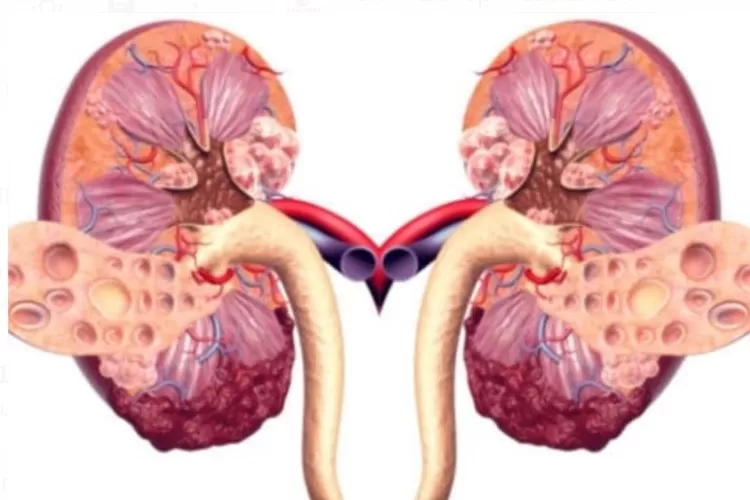

JAKARTA INSIDER – Ginjal merupakan salah satu organ terpenting dalam tubuh manusia. Fungsi utama ginjal adalah menyaring senyawa racun dari darah.

Racun-racun dapat menyebar ke seluruh tubuh apabila ginjal tidak bekerja dengan baik dan tidak dirawat kesehatannya.

Ginjal adalah yang berurusan dengan air, namun ginjal juga memiliki energi panas di dalamnya.

Masalah di ginjal terjadi jika panas di ginjal dan dingin yang lebih kuat atau mendominasi.